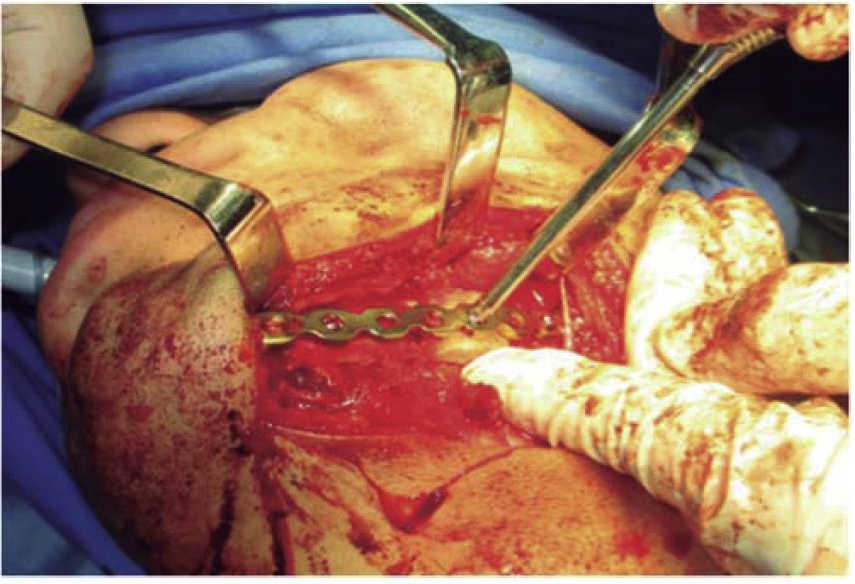

El segundo tiempo quirúrgico se realiza a los siete días mediante un abordaje extraoral. Se reduce la fractura y se fijan bordes óseos mediante una placa de reconstrucción mandibular 2.4 precontorneada (Figura 6). Previo al cierre de los tejidos se corrobora estabilidad oclusal y se retiran los arcos barra (Figura 7). El paciente permanece hospitalizado por siete días, con buena oclusión, adecuada cicatrización, se retiran puntos de sutura, se toma estudio de control y se otorga el alta médica. No acude a controles por encontrarse privado de su libertad.

En los tres casos presentados se inicia con valoración cardiopulmonar, manejo de vía aérea, control hemodinámico, ventilación, discapacidad neurológica y daños específicos.9-11 Con la exploración física determinamos la extensión de daño en los tejidos, presencia de orificios de entrada y salida para descartar la presencia de bala al interior en una cavidad o tejido (caso 2). El manejo maxilofacial se inicia con desbridaje conservador, lavado, extracción de restos radiculares, sutura y estabilización oclusal. La reducción y fijación de las fracturas (caso 1 y 3) se realizó en un segundo acto quirúrgico con placas de reconstrucción. En los casos expuestos se observó una buena evolución, una cicatriz ósea favorable y la necesidad de continuar con una rehabilitación oral mediante prótesis o implantes osteointegrados. Las complicaciones y secuelas son comunes y surgen por lo general a causa de la severidad de las lesiones iniciales, retraso en el tratamiento por riesgo vital o estado sistémico del paciente.